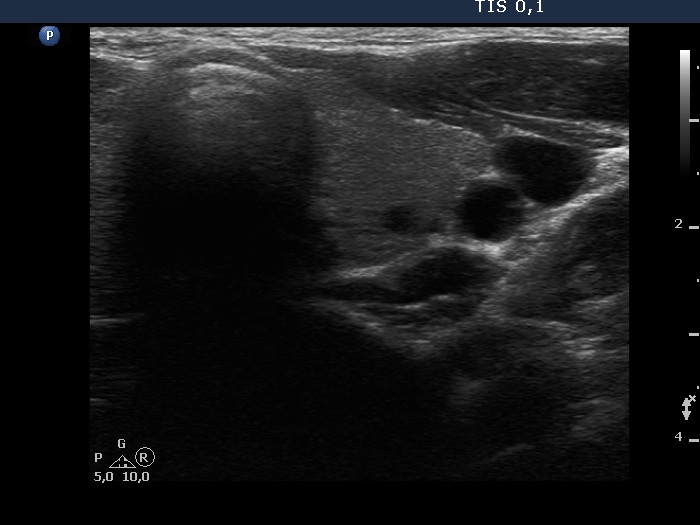

Left lobe, transverse scan. Despite the presence of a small cystic lesion, this lobe should be regarded intact.